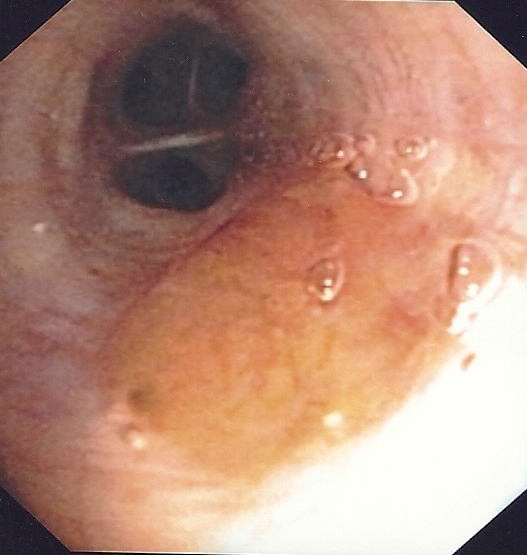

Small quantity of secretions